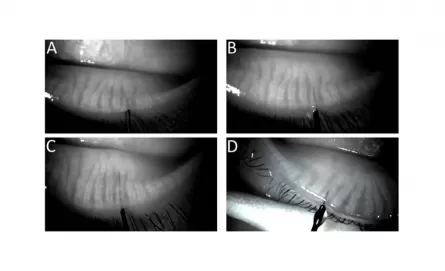

MediWorks S390L Slit Lamp Supports Real-time Infrared Video Feed for o-MGD Probing

The team of Dr. Steven L Maskin, from Dry Eye and Cornea Treatment Center, Tampa, FL. in the United States, published their latest research titled Meibography Guided Intraductal Meibomian Gland Probing Using Real-Time Infrared Video Feed on CLINICAL SCIENCE.

Meibography guided intraductal meibomian gland probing using real-time infrared video feed

Obstructive meibomian gland dysfunction (MGD) is considered the most frequent cause of dry eye in the world. We recently reported 67% of all probed (expressible and non- expressible) glands demonstrated FFFUR within 1 mm of the orifice and over 90% within 2 mm suggesting that expressible glands were just as likely to have occult obstruction as non-expressible glands to have obvious obstruction.